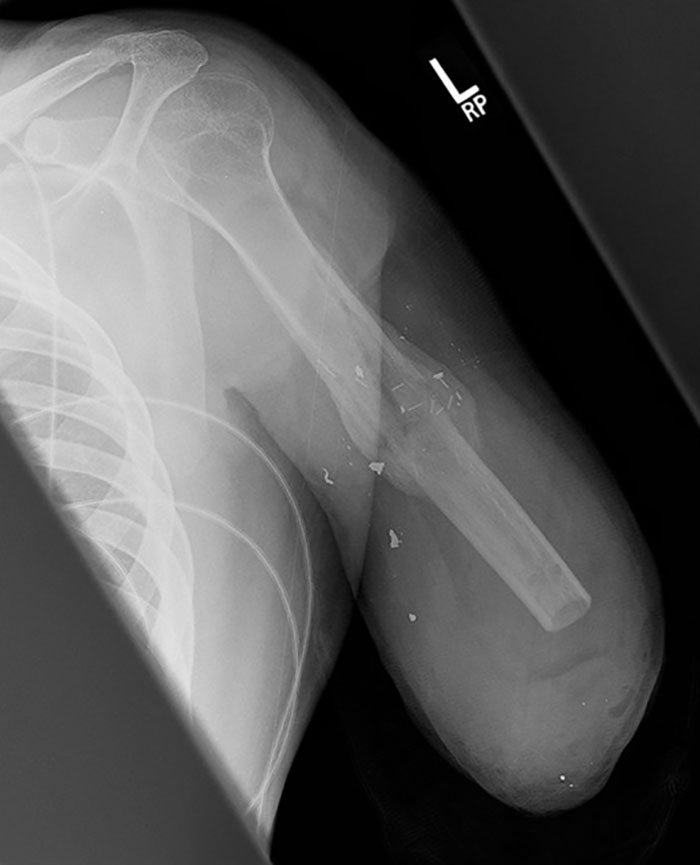

My Friends X-Ray After Being Shot With A Shotgun

That birdshot hit with quite a bit of force to have broken his humerus.